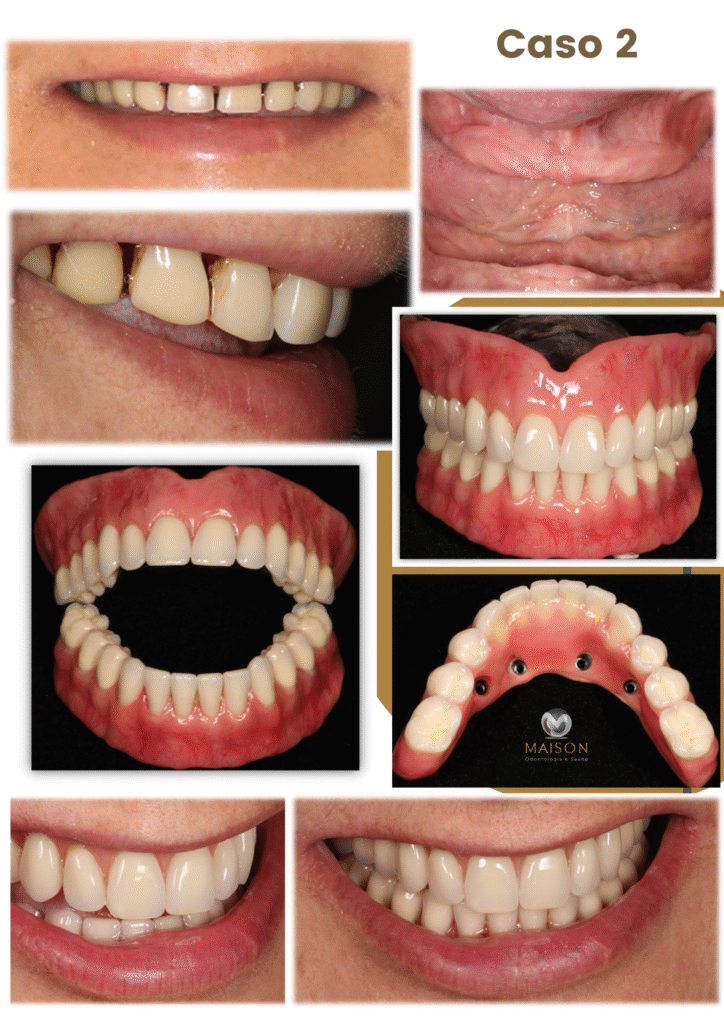

Transformação do Sorriso

Veja o que Nossos Pacientes

25 Anos de Experiência

Transformando Sorrisos

Com mais de 25 anos de experiência na área odontológica, o Dr. Giancarlo, Dra Morgana e equipe se destacam como um profissionais altamente qualificados e comprometidos com a saúde bucal de seus pacientes. Reconhecidos por sua abordagem cuidadosa e profissionalismo exemplar, eles se tornaram referência na área por oferecer tratamentos eficazes e humanizados.

- Técnicas Avançadas de Reabilitação Oral: Implantes Unitários, Múltiplos, Overdenture, Protocolo, Técnica Facco no osso Zigomático; realizamos todos o tipos de próteses sobre implante.